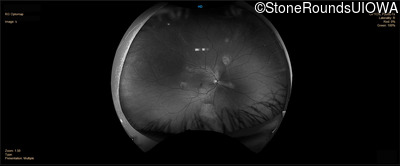

Infrared Fundus Photograph - Right - 20/20 -1 sc

Exemplar

Infrared Fundus Photograph - Left - 20/20 -1 sc